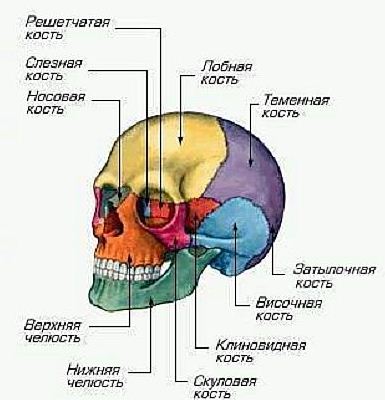

К скелету нижней части относят тазовую и бедренные кости, надколенники, большеберцовую кость, малоберцовую кость, а также кость стопы. В основном большинство травм связанных с костями происходит именно с скелетами верхней и нижней частей. Это вполне объяснимо, так как эти скелеты наиболее активно участвуют в передвижении человека, и они чаще всего подвергаются воздействию со стороны. Реже, но все равно бывают различные травмы черепа. Сам череп представлен на рисунке ниже:

Рис. 2.4. Череп

Как можно увидеть череп состоит их решетчатой кости, лобной кости, теменной кости, слезной кости, носовой кости, затылочной кости, височной кости, скуловой кости, нижней челюсти, верхней челюсти, а также клиновидной кости. Так как подвижной частью в черепе является нижняя челюсть, то с ней наиболее часто случаются различные травмы, которые могут серьезно сказаться на здоровье человека. Обычно травмы нижней челюсти случаются при ударах. Интересен и тот факт, что все кости черепа соединены между собой с помощью зубчатых швов. Эти швы помогают наиболее плотно скрепить черепные кости.